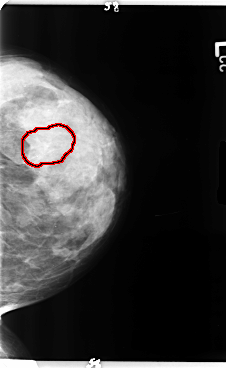

B_3358_1.LEFT_MLO

LEFT_MLO LINES 4784 PIXELS_PER_LINE 2816 BITS_PER_PIXEL 12 RESOLUTION 50 OVERLAY

FILE: B_3358_1.LEFT_MLO.OVERLAY

TOTAL_ABNORMALITIES 1

ABNORMALITY 1

LESION_TYPE CALCIFICATION TYPE ROUND_AND_REGULAR-PUNCTATE-AMORPHOUS DISTRIBUTION REGIONAL

ASSESSMENT 4

SUBTLETY 3

PATHOLOGY BENIGN

TOTAL_OUTLINES 1

BOUNDARY